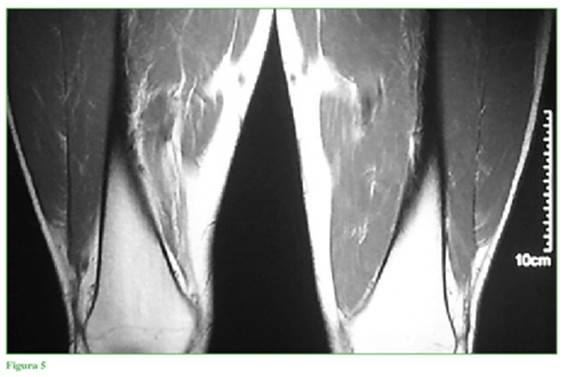

El estudio gold standard es la resonancia magnética nuclear, la que informó ausencia completa del vasto medial oblicuo (VMO) y diagnóstico presuntivo de agenesia completa de ese músculo en cortes axiales, sagitales y coronales en T1 y T2 (Figuras 4 a 8). Cortes coronales a diferentes alturas comparativas de ambos muslos en la región del tercio medio distal (Figuras 5 a 8).

Falta la representación habitual del músculo vasto medial derecho en toda su extensión, sugestivo de hipotrofia grave/agenesia muscular; vasto intermedio derecho, vasto lateral y recto anterior de grosor y señal de resonancia preservada. No se identifican alteraciones del trofismo muscular, ni señal de resolución de los músculos del grupo medial y posterior derecho, ni a nivel del muslo izquierdo. No se observan lesiones ni alteraciones del paquete vascular femoral. Llama la atención una asimetría en la masa muscular de la cara interna del muslo; no se identifica el músculo vasto medial y no hay signos de edema, colecciones, ni alteraciones de planos grasos.